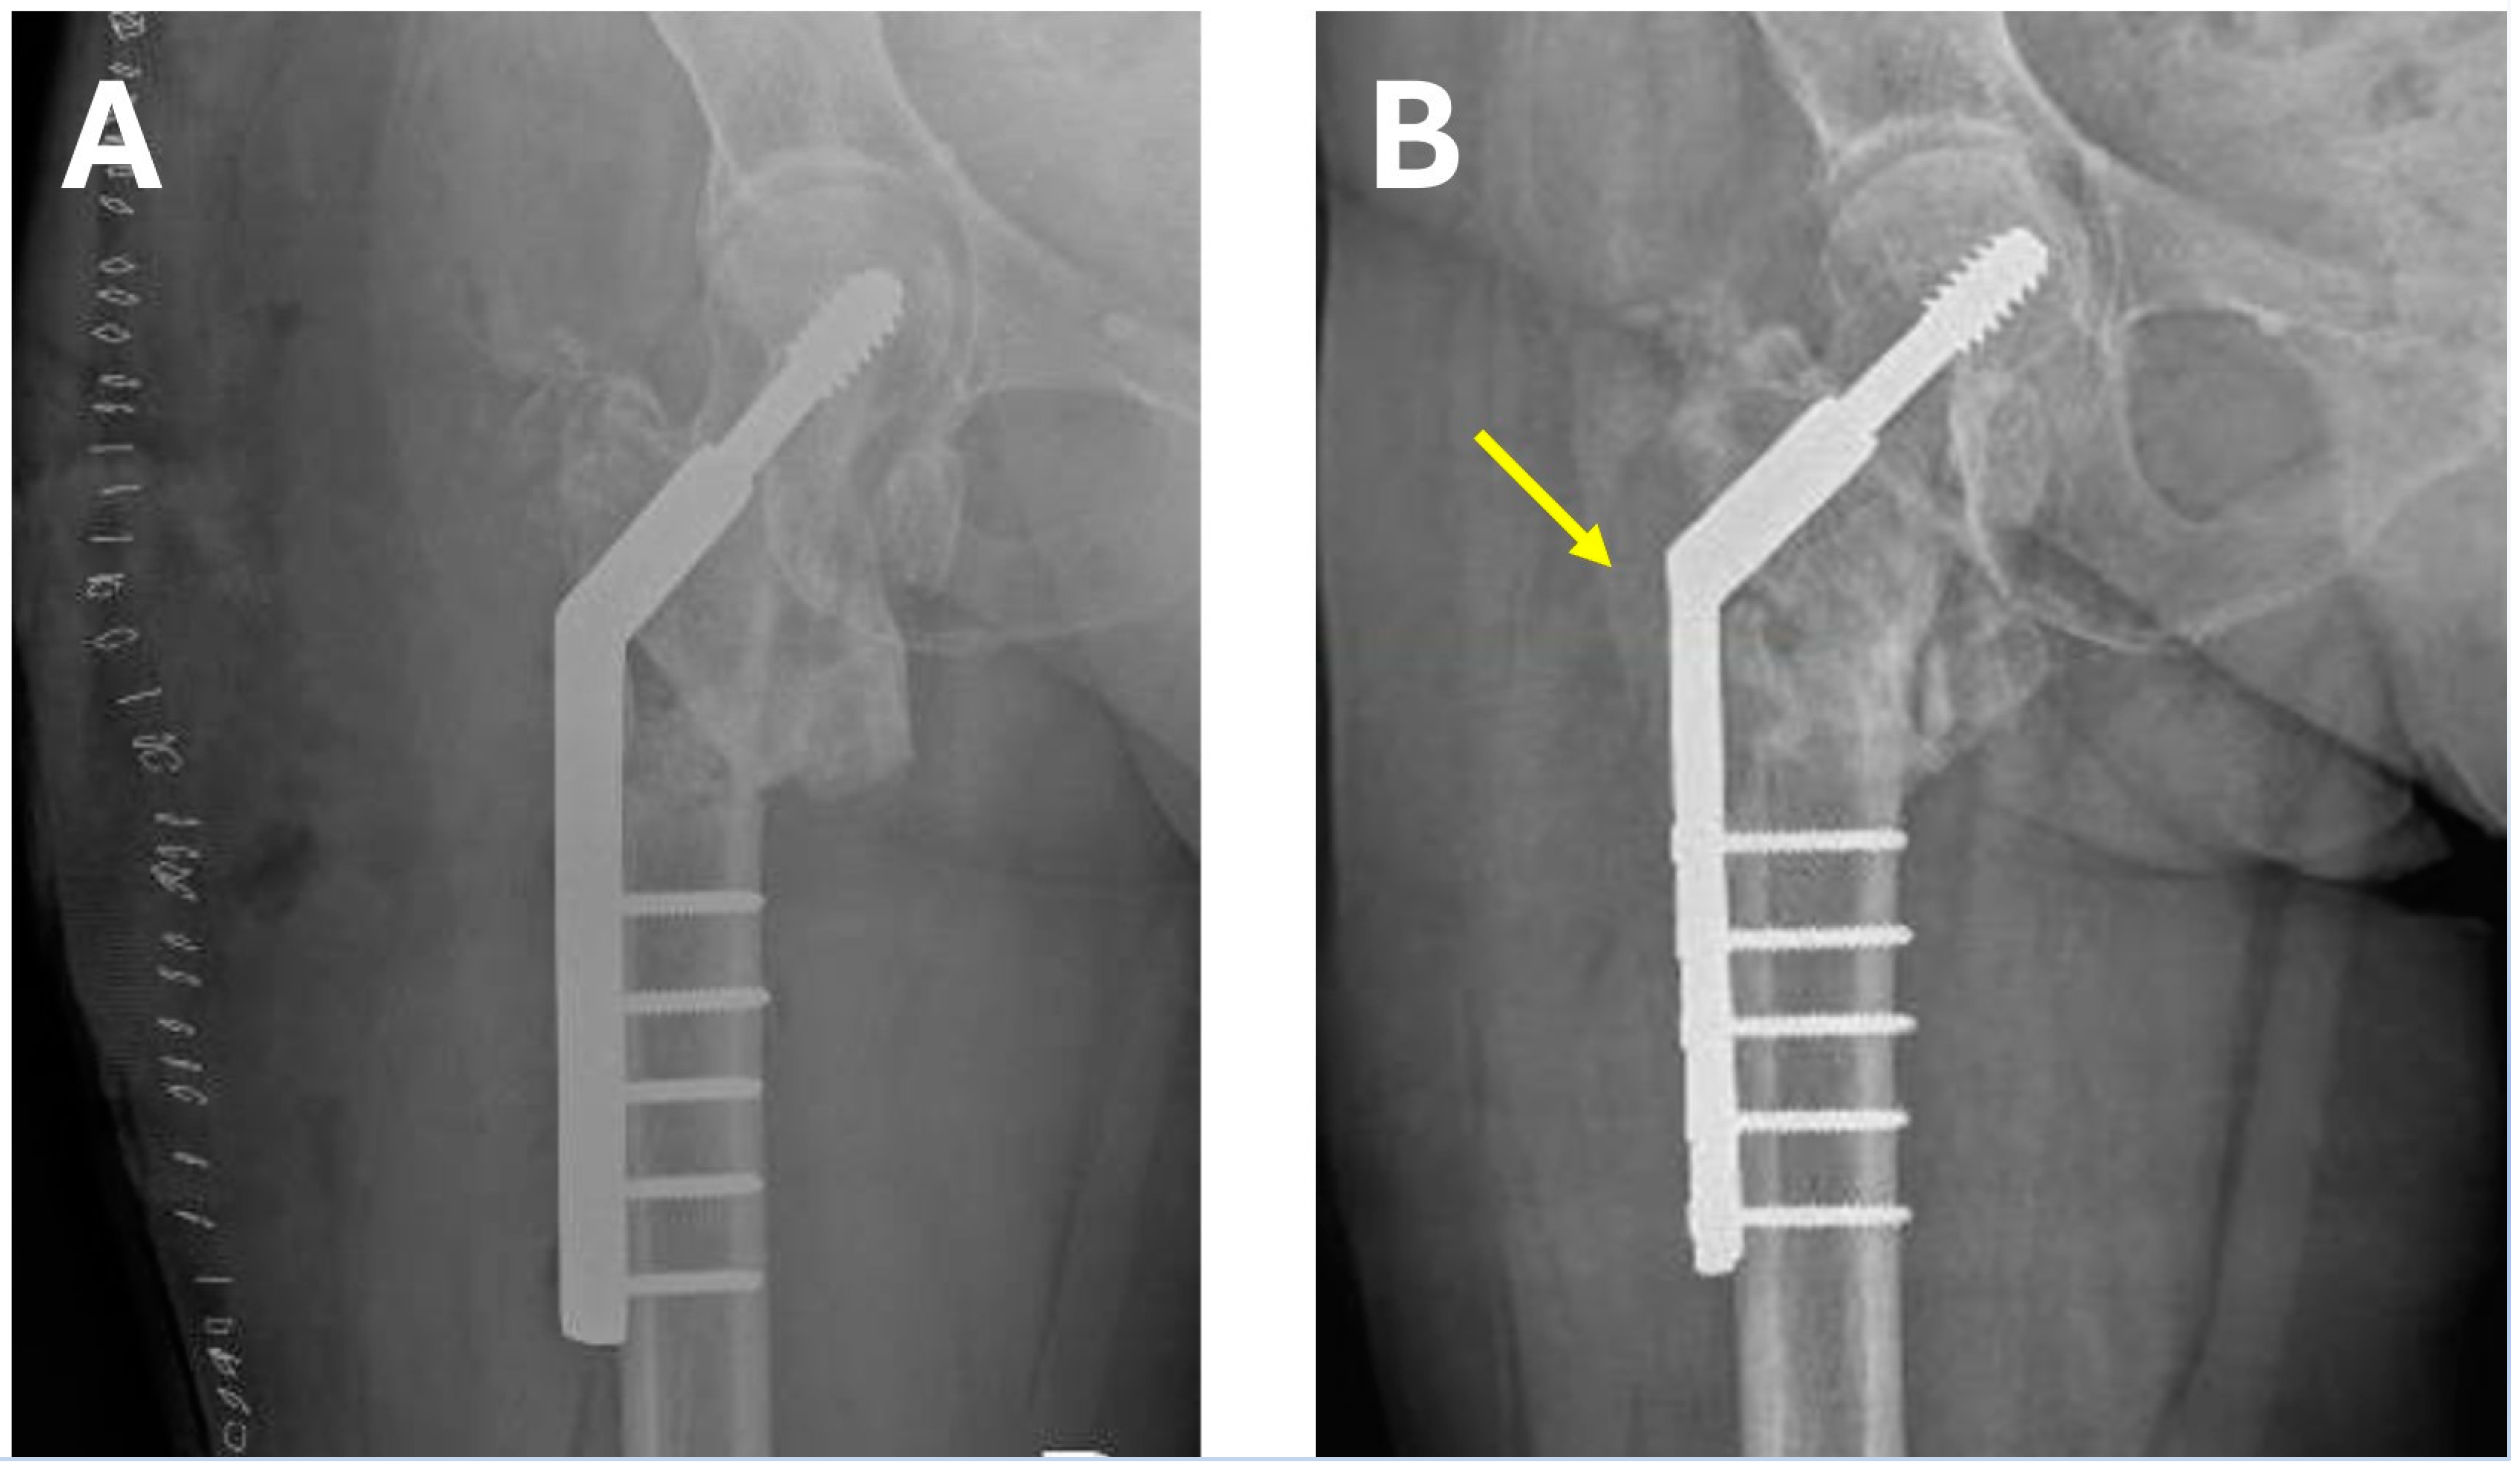

| Femoral neck angle pre-surgery * | 122° | 128° | 125° | 110° | 115° | 120° (110–122) |

| Pre-surgery offset (mm) * | 59 | 42 | 50 | 54 | 47 | 50.4 (42–59) |

| Vertical distance nonunion-head pre-surgery (mm) * | 57 | 43 | 32 | 46 | 40 | 43.6 (32–57) |

| Limb length discrepancy (mm) * | 12 | 8 | 9 | 4 | 7 | 8 (4–12) |

| Femoral neck angle post-surgery * | 142° | 150° | 150° | 147° | 145° | 146.8 (142–150) |

| Post-surgery offset (mm) * | 24 | 19 | 18 | 20 | 17 | 19.6 (17–24) |

| Vertical distance nonunion–head post-surgery (mm) * | 65 | 55 | 38 | 52 | 48 | 51.6 (38–65) |

| Postoperative leg lengthening (mm) * | 8 | 12 | 6 | 6 | 8 | 8 (6–12) |